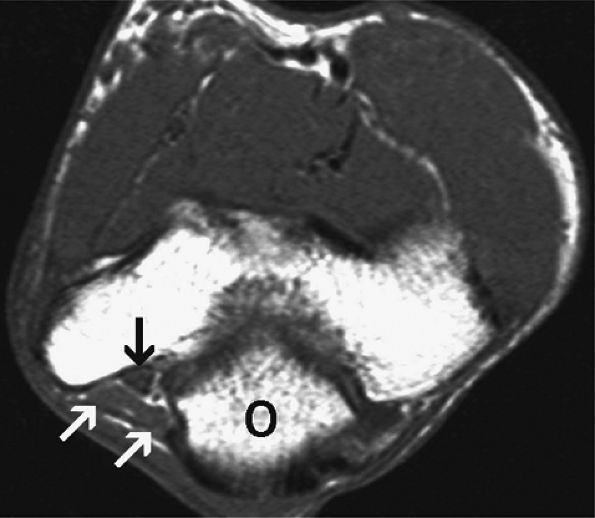

FIGURE 12.21 ● Anconeus epitrochlearis muscle. Axial T1-weighted image demonstrates the accessory muscle (white arrows) effacing the fat within the cubital tunnel. The ulnar nerve (black arrow) is normal. O, olecranon.

|